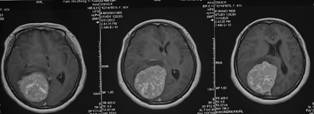

术后核磁共振检查提示肿瘤完全切除